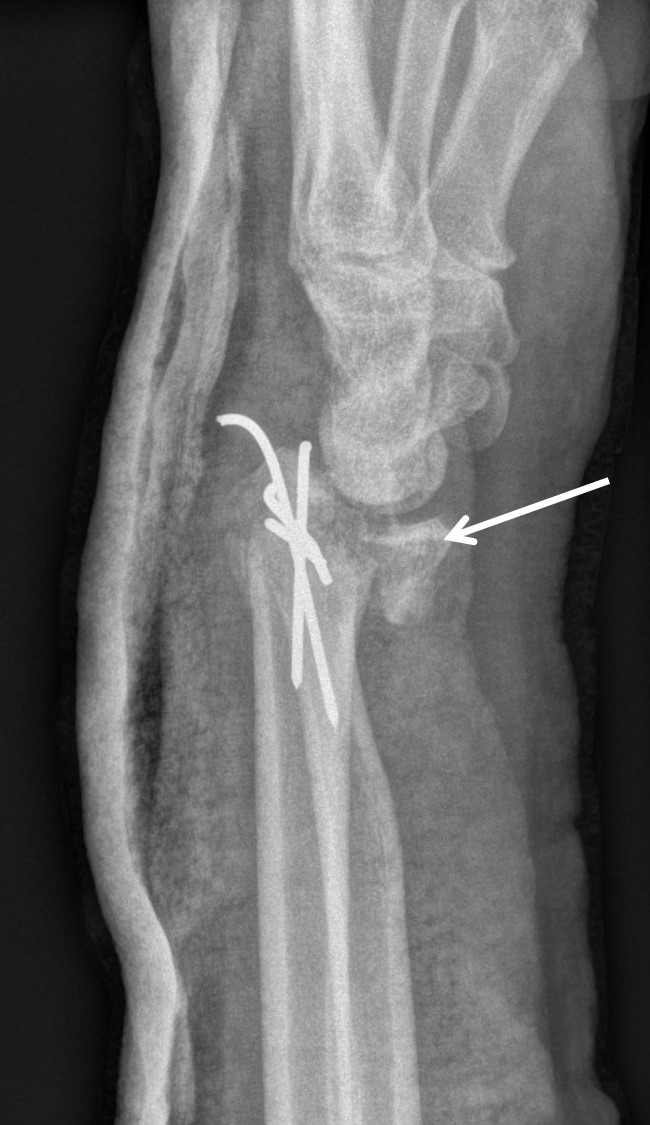

Treatment of neglected, displaced or united distal radial fractures (DRFs) is difficult, because it requires either wedging the almost consolidated fracture and reduction to the correct position, or cutting the united bone and putting it in the correct position (corrective osteotomy). Both treatments are associated with the risk of failure and complications. The paper presents a case of almost fully united DRF in a man, in whom 5 weeks after the injury, and after unsuccessful primary fixation with K-wires, the bone fragments were surgically wedged, aligned and fixed with a palmar plate. The result of treatment after 2 months was satisfactory. Early surgery allowed for a significant shortening of the recovery period and allowed the patient to return to work.